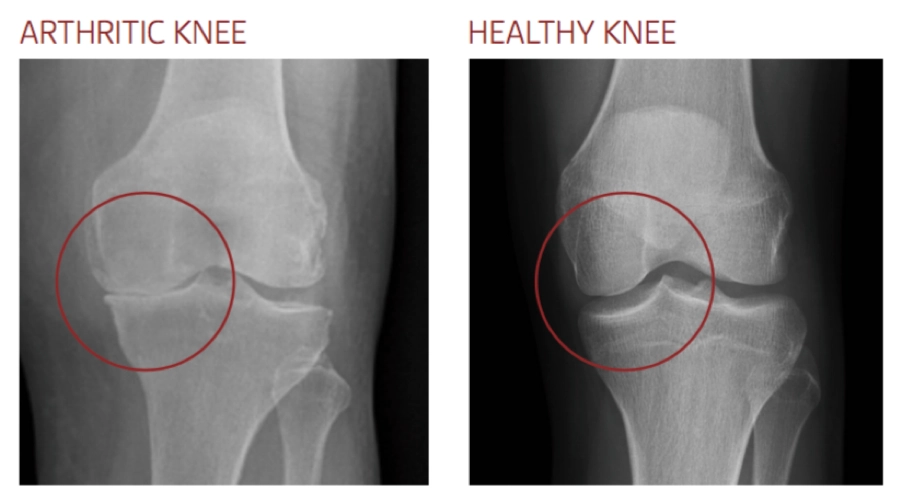

Knee arthritis—most commonly knee osteoarthritis—occurs when the smooth cartilage that lines the knee joint gradually wears away. Without this protective cushion, the bones rub together, causing pain, swelling and reduced movement.

X-rays are usually sufficient to diagnose knee arthritis

- X-rays are usually sufficient to diagnose knee arthritis

- MRI may be requested if there is concern about a meniscal tear, ligament injury or other soft-tissue cause of pain